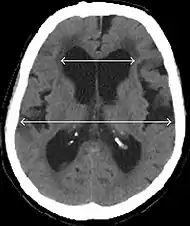

Evan's index is the ratio of maximum width of the frontal horns to the maximum width of the inner table of the cranium. An Evan's index more than 0.31 indicates hydrocephalus.[8]

Typical imaging findings in normal pressure hydrocephalus versus brain atrophy.[9]

Normal pressure hydrocephalusBrain atrophy

Preferable projectionCoronal plane at the level of the posterior commissure of the brain.

Modality in this exampleCTMRI